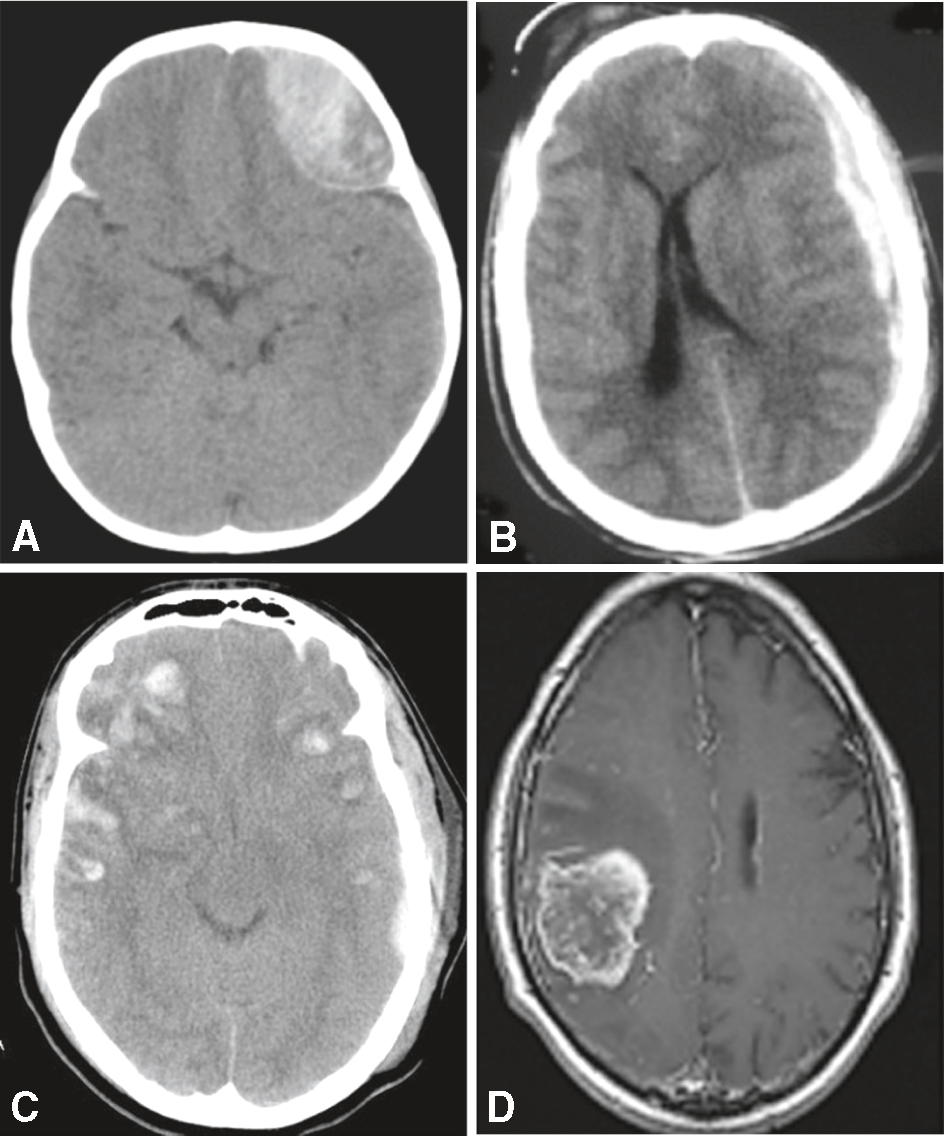

Ils sont répertoriés dans le tableau 5.2 et illustrés à la figure 5.2.

Exemples de causes de déficit neurologique récent en imagerie. A. Scanner cérébral sans injection. Hématome extradural (hyperdensité biconvexe). B. Scanner cérébral sans injection. Hématome sous-dural aigu (hyperdensité en croissant). C. Scanner cérébral sans injection. Contusion hémorragique (hypo- et hyperdensités). D. IRM cérébrale (T1 avec gadolinium). Tumeur cérébrale (lésion rehaussée par le produit de contraste).

L'image montre quatre scans cérébraux, chacun étiqueté de A à D. Ces scans sont des exemples de causes de déficit neurologique récent. Image A : Montre une hémorragie intracérébrale, qui est une accumulation de sang dans le cerveau due à la rupture d'un vaisseau sanguin. Cela peut causer des dommages aux tissus cérébraux environnants et entraîner des déficits neurologiques. Image B : Illustre un infarctus cérébral, également connu comme l'accident vasculaire cérébral ischémique, qui se produit lorsque l'apport sanguin à une partie du cerveau est interrompu, entraînant la mort des cellules cérébrales dans la zone affectée. Image C : Montre un œdème cérébral, un gonflement du cerveau causé par une accumulation de liquide. Cela peut être dû à des traumatismes crâniens, des infections, ou des tumeurs, entraînant une augmentation de la pression intracrânienne et des déficits neurologiques. Image D : Montre une tumeur cérébrale, une masse anormale de cellules dans le cerveau. Les tumeurs peuvent être bénignes ou malignes et causer des symptômes neurologiques en comprimant les structures cérébrales environnantes. Chaque image illustre une pathologie différente pouvant entraîner des déficits neurologiques récents, soulignant l'importance de l'imagerie médicale pour diagnostiquer et gérer ces conditions